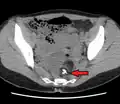

A small (4 cm) dermoid cyst of an ovary, discovered during a C-section

While all ovarian cysts can range in size from very small to quite large, dermoid cysts are not classified as functional cysts. Dermoid cysts originate from pluripotent germ cells (which are present at birth) that differentiate abnormally, developing characteristics of mature dermal cells. Complications exist, such as torsion (twisting), rupture, and infection, although their incidence is rare. Dermoid ovarian cysts which are larger present complications which might require removal by either laparoscopy or laparotomy (traditional surgery).[3][4] Rarely, a dermoid cyst can develop in the vagina.[5][6][7]

The association of dermoid cysts with pregnancy has been increasingly reported. They usually present the dilemma of weighing the risks of surgery and anesthesia versus the risks of untreated adnexal mass. Most references state that it is more feasible to treat bilateral dermoid cysts of the ovaries discovered during pregnancy if they grow beyond 6 cm in diameter.